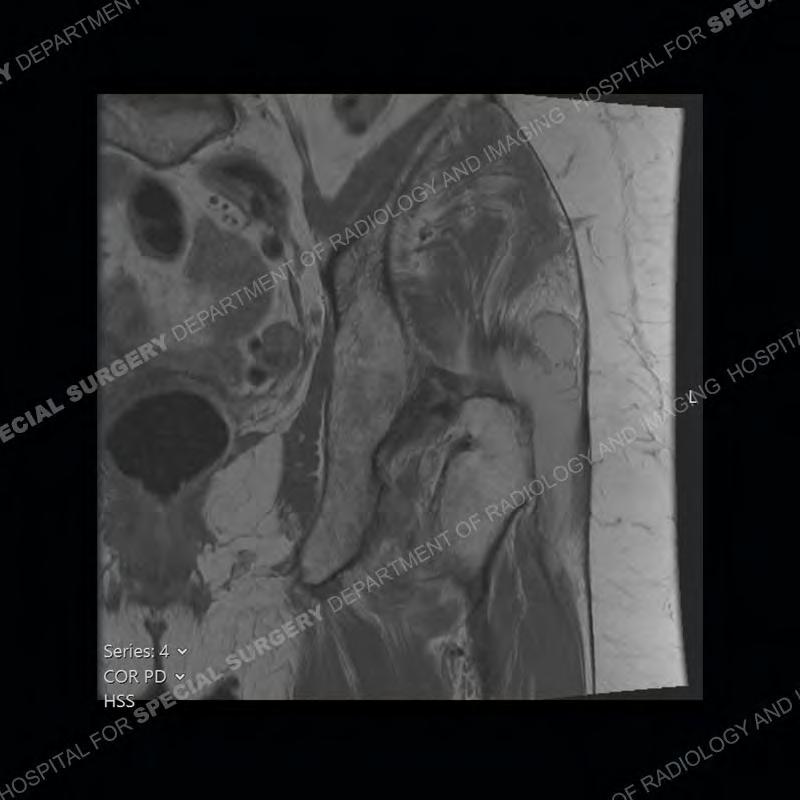

The radiograph is not particularly contributory in this case. The MRI demonstrates markedly abnormal architecture of the gluteus minimus and anterolateral band of the gluteus medius. Portions of the tendons are high signal, portions are highly attenuated, and portions are disrupted. A large, complex fluid collection is present in the adjacent soft tissue.

Diagnosis: Gluteal Tendinosis and Disruption with Complex Trochanteric Bursal Collection

Not as much of a diagnostic dilemma as many of the other cases shown but just a nice example of the pathology seen of the gluteal tendons and a cause of trochanteric pain. Although, frequently thought of in isolation, trochanteric bursitis or bursal thickening is much more commonly a reactive change to underlying pathology of the subjacent gluteal tendons. The gluteus medius is divided into a posterior band and an anterolateral band. Tendinosis and partial tearing very commonly will involve the gluteus minimus and especially the more posterior fibers and then propagate into the anterior lateral band of the gluteus medius. Involvement of the posterior band of the medius is much less common and engenders a marked degree of functional impairment.

The bursae about the greater trochanter can be a little bit confusing especially given the terminology. Trochanteric bursitis is implied to mean the subgluteus maximus bursa which is present deep to the maximus and just lateral/superficial to the trochanter. That is the bursa involved in this case. In this case the complexity of the bursa relates to the tendon tearing with inflammatory change and probably hemorrhage accounting for the complexity. Two other, less frequently involved bursa are also present. The subgluteus medius and subgluteus minimus bursa are found just deep to the named tendons. Although pathology does frequently follow the previously described pattern it is possible to have isolated pathology to either the medius or minimus.